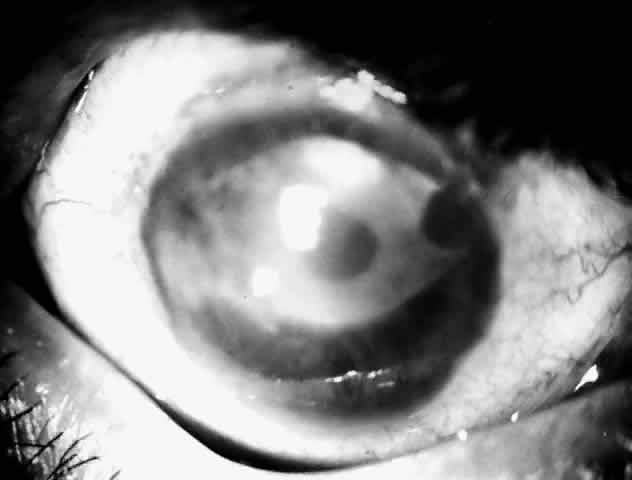

Active corneal infections in advanced stages are encountered more often by corneal surgeons in developing countries compared with their counterparts in developed countries (Fig. 8). The extent of corneal involvement associated with other intraocular damage often compromises the success of corneal transplantation. In a series from our institution, the success rate for graft clarity was poorer24 compared with other series.25 Ophthalmologists involved in corneal surgery should be familiar with this information and be prepared for the necessary intraoperative manipulations (Fig. 9).

Fig. 9. Large central perforation in a case of infectious keratitis.